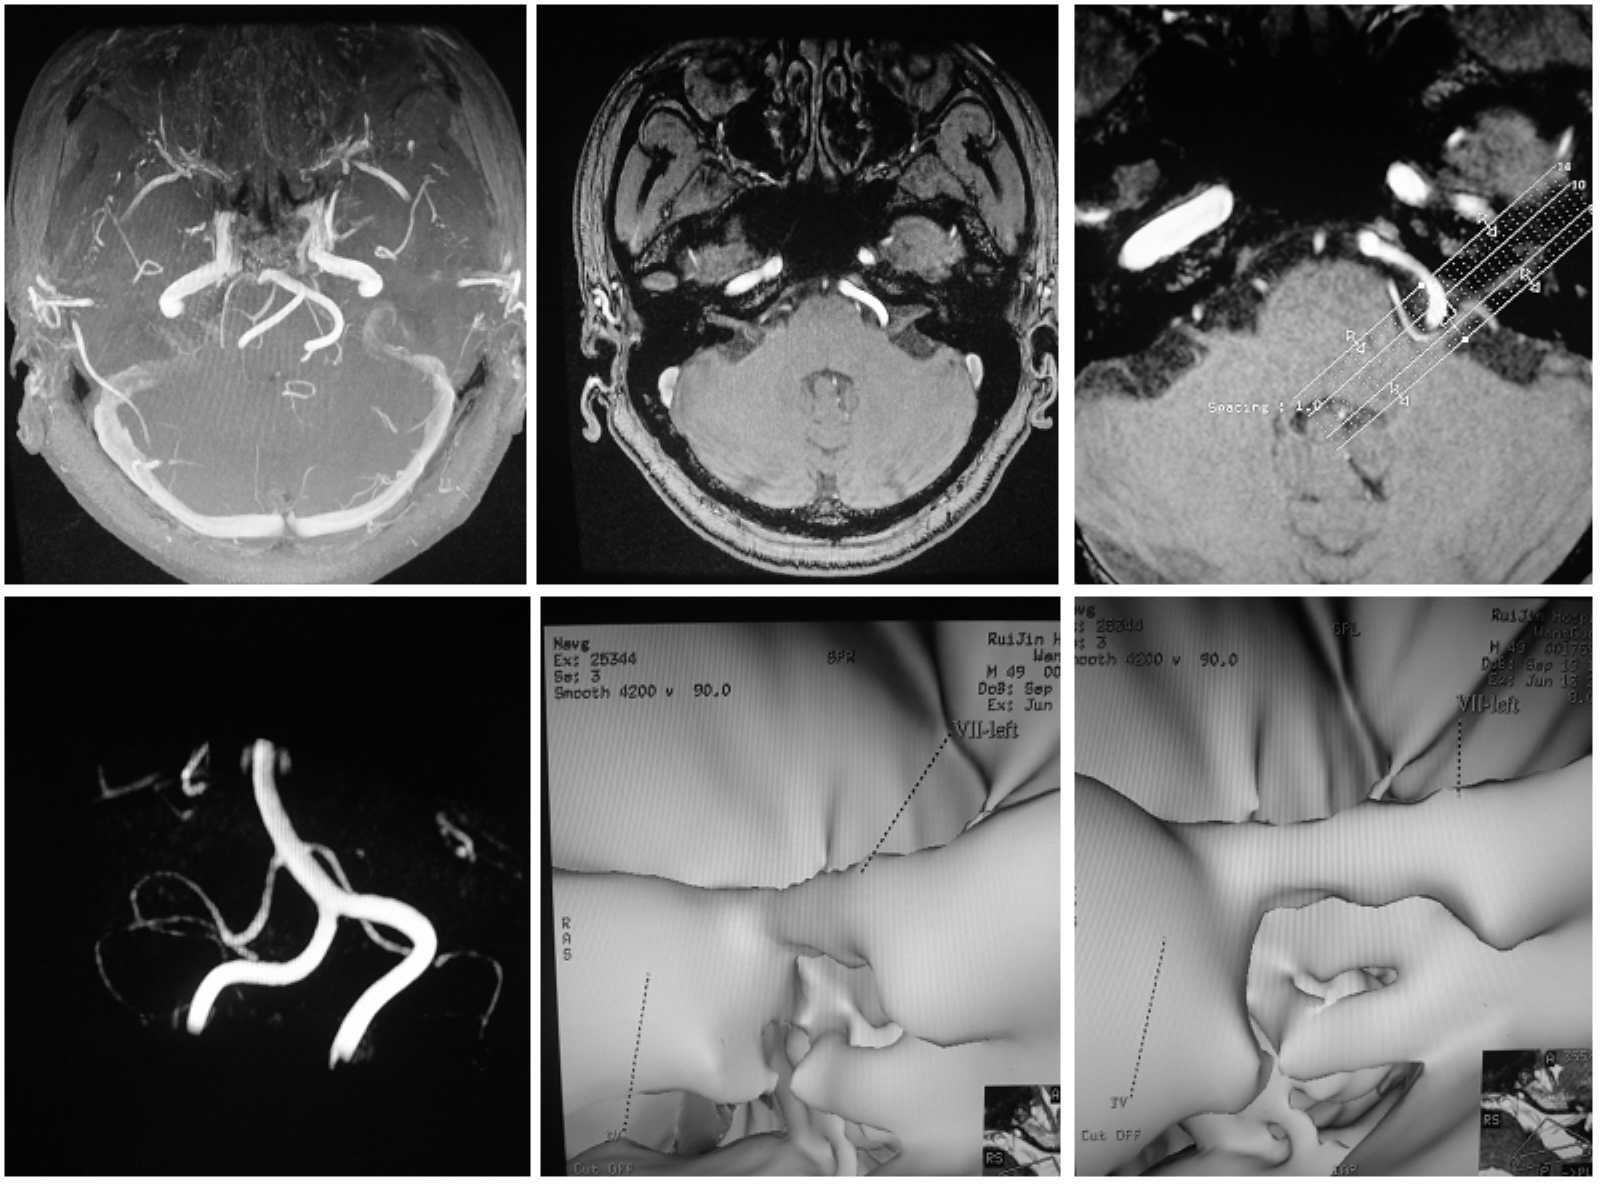

患者39岁,左侧面肌痉挛6年,服用药物卡马西平及盐酸硫必利无效,随着程度的加剧,接受了“微血管减压术”。“微血管减压术”出奇制胜,病人面部肌肉反复的不自主抽动消失。

面肌痉挛、三叉神经痛的发病时间顺序是有规律可循的。绝大部分患者首先发生面肌痉挛,然后发生三叉神经痛,考虑可能与椎基底动脉的迂曲硬化有关。椎基底动脉连接部位常于桥延沟,与面神经较靠近,易于先压迫面神经而造成面肌痉挛。随着动脉硬化的发展,以及随年龄增长而发生的不同程度的脑萎缩,扭曲硬化的椎基底动脉还会压迫三叉神经而造成三叉神经痛。

术前检查